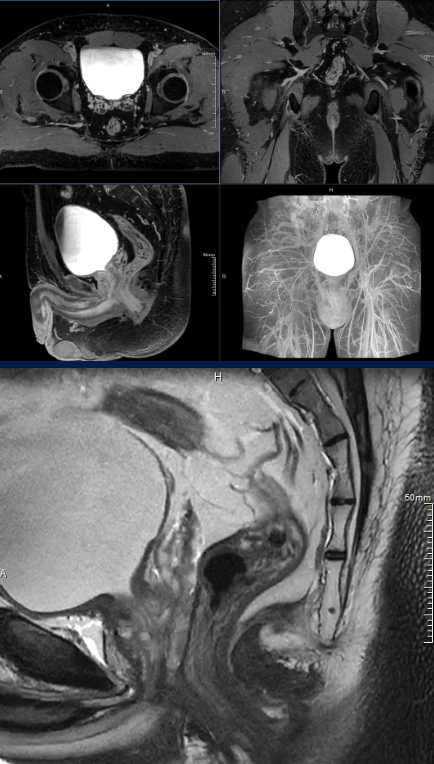

12 月,高尚健康集团上海中心与上海长征医院携手,以「基于 PET/MR 一体化影像数据及 AI 后处理的盆腔解剖学三维重建手术规划的临床实践与应用」为研究方向,通过对上百例患者开展结直肠专项筛查,完成了相应的科研论证工作。